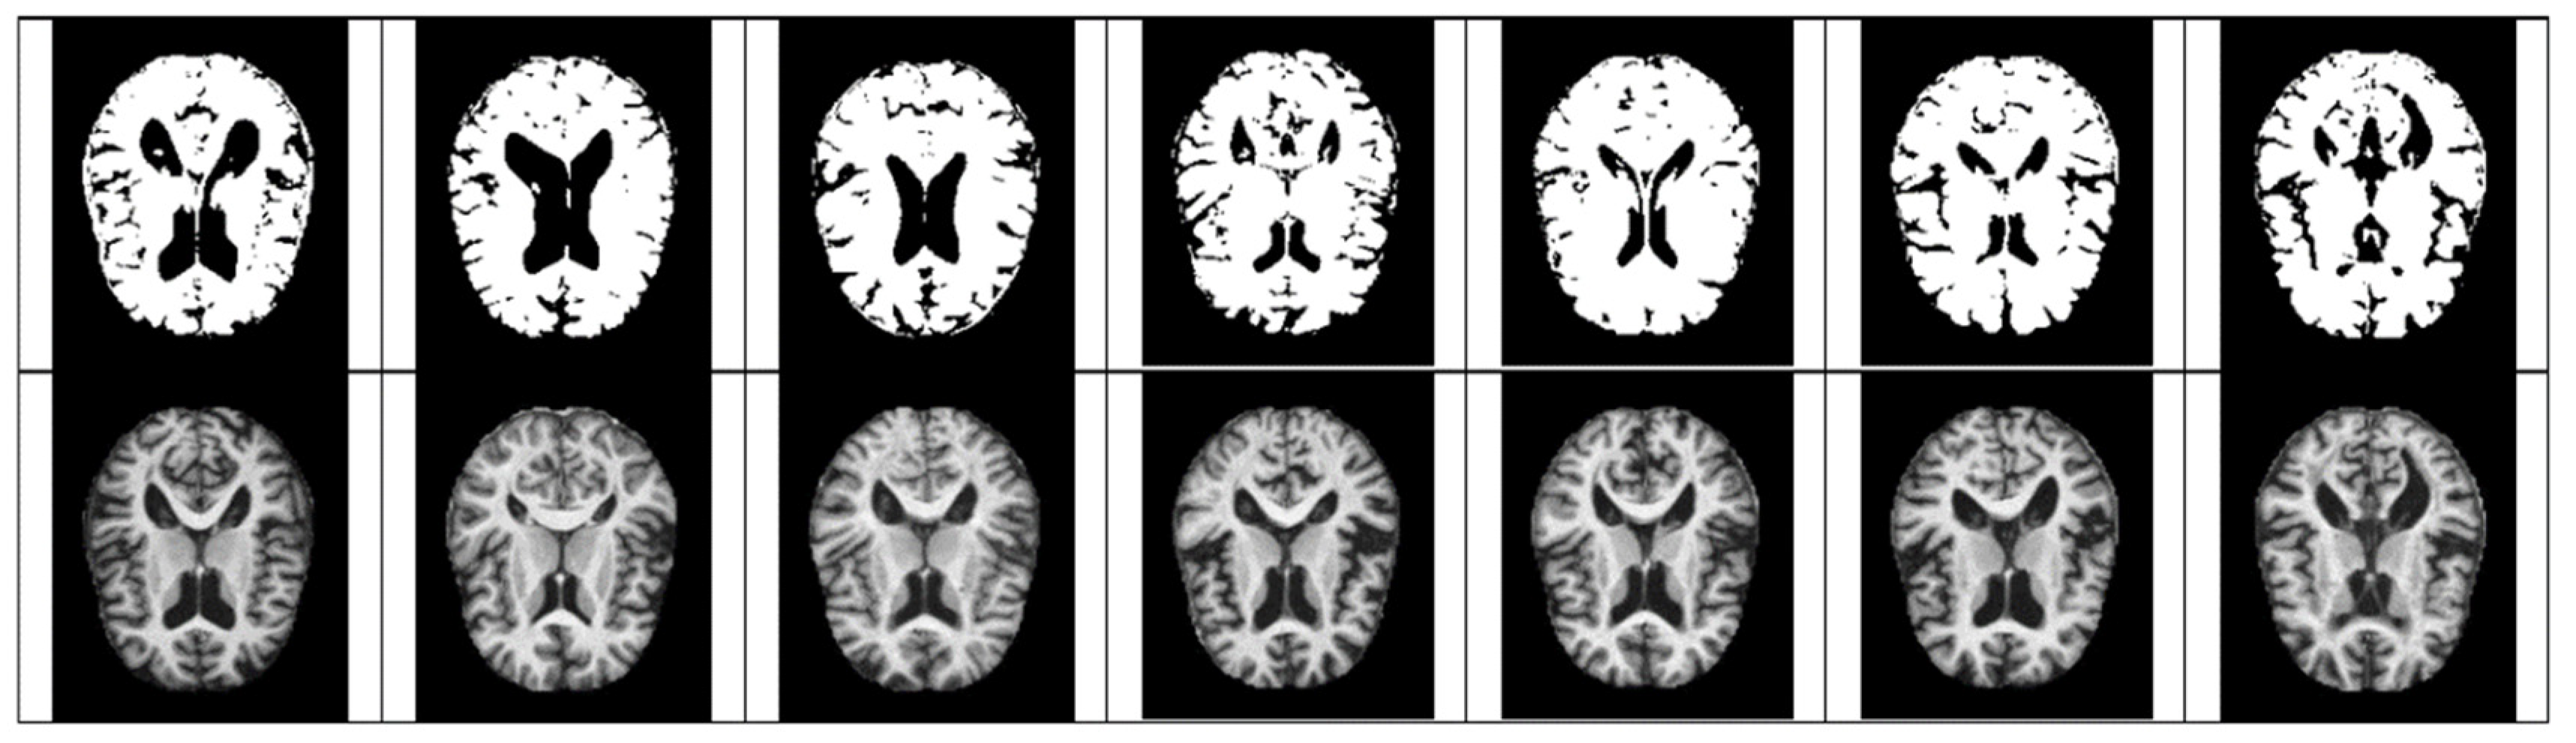

- As mentioned above, the method of diagnosing AD on MRI images compares the size of the hippocampus. However, due to the nature of the existing CNN model, it is difficult to detect because it is not sensitive to image dispersion. Therefore, additional processing of the color space of the image is required.

- For Z-score normalization, the interval to which each pixel belongs is converted to [−1, 1], and for min–max, it is converted to [0, 1]. During the computation of the convolutional neural network, the pixel intensity of [0, 255] is adjusted for fast convergence and accurate feature extraction.

- The size space of pixels constituting the Alzheimer’s MRI data set is [0, 255]. Among them, patients with AD with reduced hippocampus will have more pixels close to zero than normal people. On the premise of this, the average value of pixel intensities in each MRI image is set as a threshold value. Alzheimer’s should recognize changes in size contraction rather than changes in brain function. Based on this information, it is necessary to set the space as an important feature for the color information of MRI rather than a feature representing the shape of the brain.